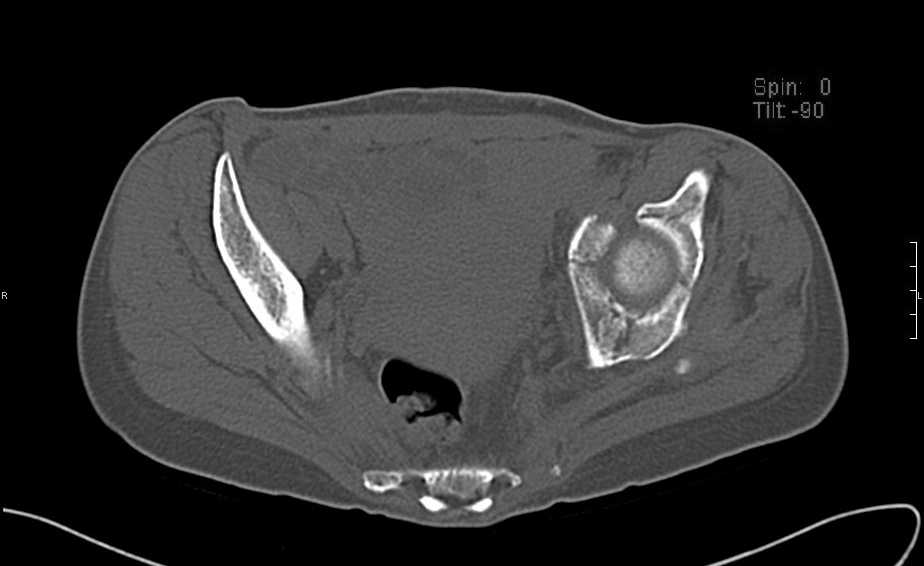

Перелом свода и основания черепа. Вертикально-нестабильное повреждение таза, осложнённое разрывом мочевого пузыря. Чрезвертельный перелом левого бедра. Перелом правой таранной кости, переломовывих правой кубовидной кости. Тупая травма живота, разрыв печени, ушиб почек. Забрюшинная гематома. В день травмы - лапаротомия, ушивание ран печени. Разрыв мочевого пузыря не диагностирован. Течение болезни осложнилось развитием мочевого затёка и обширной пред- и забрюшинной флегмоны, сформировался свищ мочевого пузыря. 19.8.2008 вскрытие, дренировние флегмоны, ревизия мочевого пузыря, обтурация мочевого свища (свищ закрылся в октябре), 1.10.2008 некрэктомия, пластика по Шеде-Лидскому правой кубовидной кости. По результатам КТ диагностирован рак правой почки (диагностическая находка), 8.10.2008 нефрэктомия справа.

Имеется вертикальное смещение левой половины таза с выраженным отведением крыла (клинически подвижности нет), несросшийся низкий двухколонный перелом левой вертлужной впадины с потерей конгруэнтности, укорочение около5 см, застарелый разрыв лонного сочленения, неправильно сросшиеся переломы обеих ветвей правой лонной кости с укорочением, патологическая подвижность лоно-седалищного фрагмента слева. Правая нижняя конечность неопорна, несмотря на то, что лежа прямую ногу поднимает, ходит на левой ноге (ортопедическая обувь) с костылями, справа тазобедренный ортез. Седалищные нервы работают. Урологи отпустили больную на 6 мес.